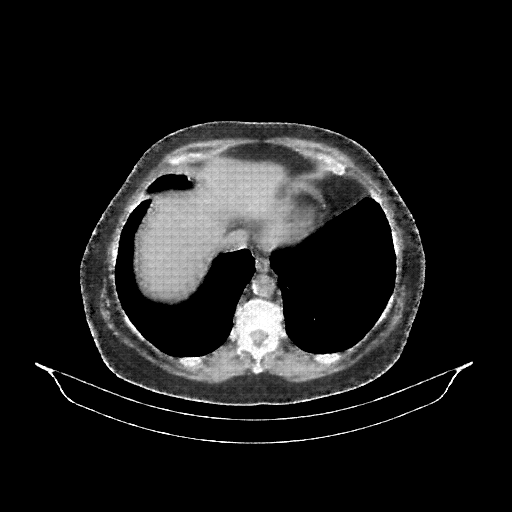

Generated VENOUS CT scan (A→B translation)

Full window (WL 1023.5, WW 4095 β†’ Low βˆ’1024, High +3071)

Mediastinum window (WL 40, WW 400 β†’ Low βˆ’160, High +240)